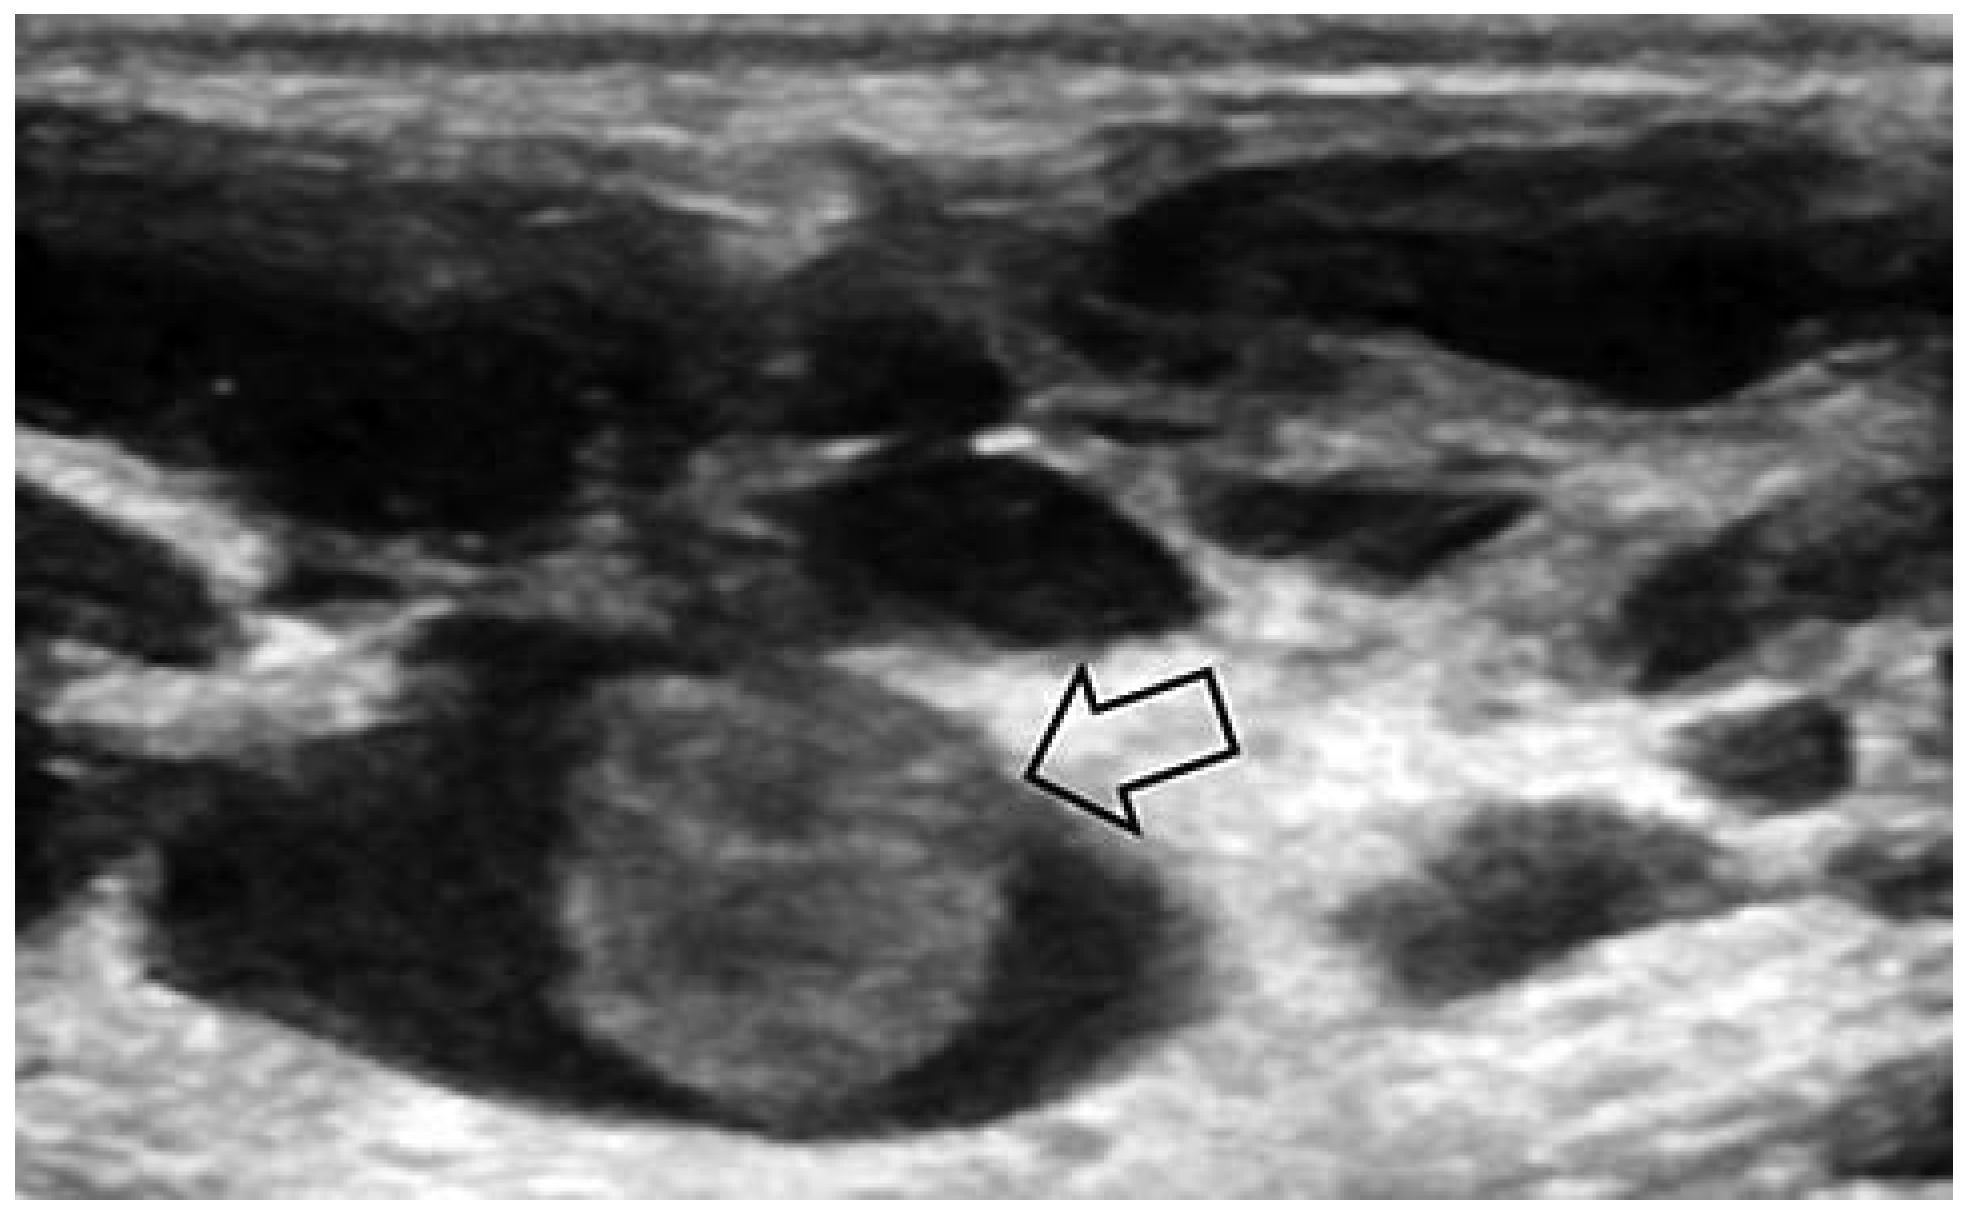

Venöse Malformationen